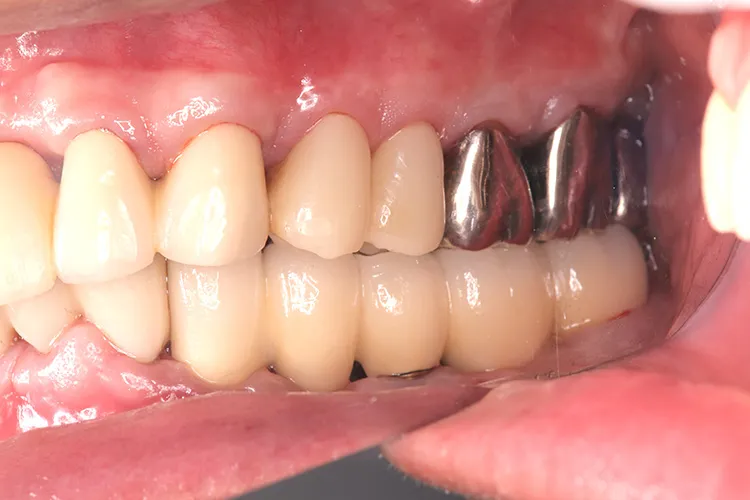

症例3/

左下5本欠損した部分をインプラント3本埋入して5本ブリッジで治したケースです。なかなかインプラントに踏み切れず、長い間入れ歯を使っておられましたが、噛みごたえがなく好きなものが食べれない上に、度々歯茎が痛んでは調整の繰り返しで快適に過ごすことができず、QOLの向上のためインプラント治療を決断されました。今ではなんでも食べれるとのことで、入れ歯で我慢しないでもっと早くインプラントにすればよかったと言っておられます。